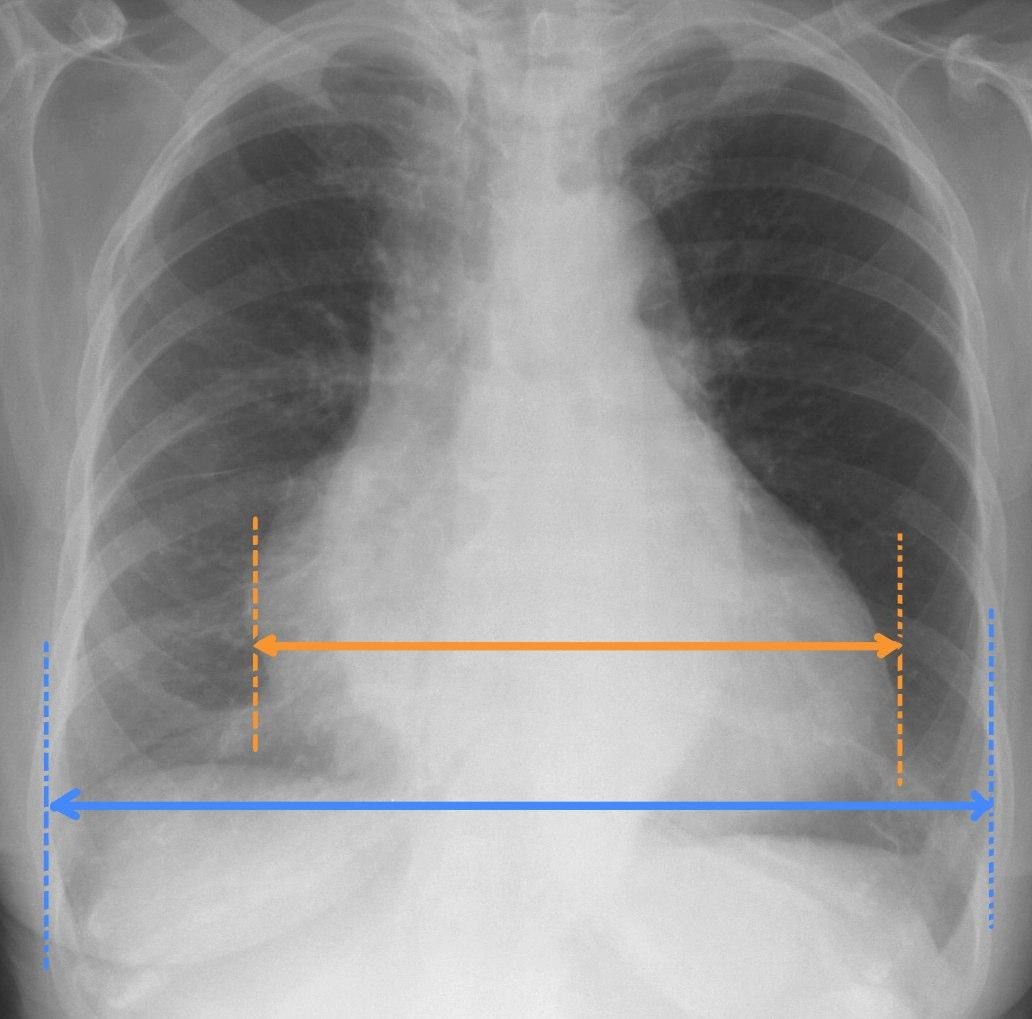

Cardiothoracic ratio

Cardiothoracic ratio: widest transverse diameter of the heart compared with the widest internal diameter of the rib cage (from inside of rib to inside of rib at the level of the diaphragm)

In most normal adults at full inspiration, the cardiothoracic ratio is less than 50%

Normal CT ratio should be less than or equal to 50%

Cardiothoracic ration